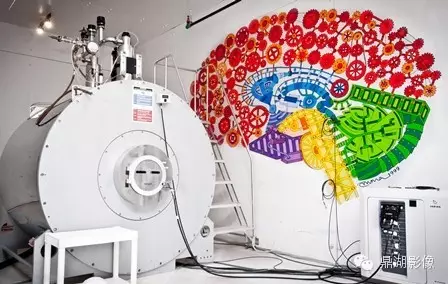

AMRIS 11T MRI

1.磁体系统:磁共振技术发展离不开磁体技术的进步,随着高场强磁体的应用,磁共振技术也进入了功能影像的时代。美国FDA已批准全身3T系统用于临床。4T系统已得到FDA无明显危险的许可。已在7T系统上对几百例健康志愿者完成无事故和无明显安全危险纪录的测试。在9.4T系统上对成年兔及其后代未观察到不良的生物效应。11T、12T系统也早已进入科研。目前磁共振的空间分辨率甚至可以达到0.2毫米的水平,清晰度可以是普通CT的5倍。另外,为了患者检查的舒适度及适应一些特殊类型人群的要求,更大口径的磁体(70cm大孔径磁体)也开始在临床普及。

(Agilent 11T MRI)